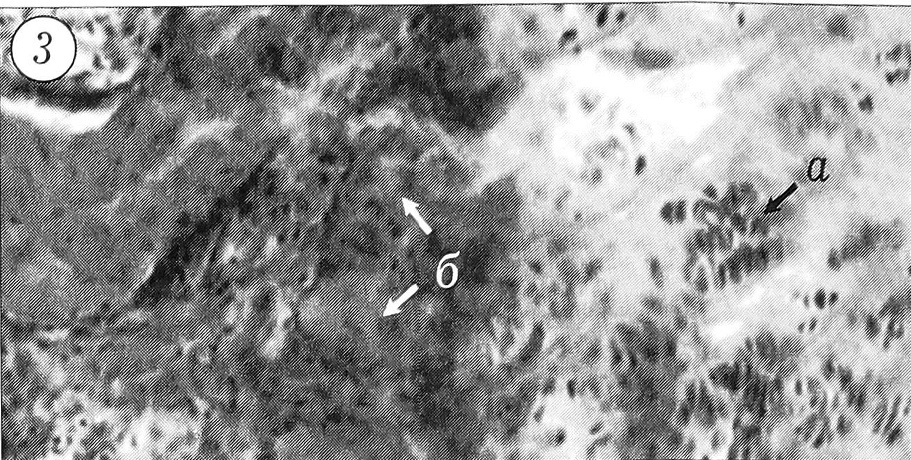

При гистологическом исследовании обнаружено, что у 6 из 16 больных тяж представлял собой типичный гиалиновый хрящ (рис. 1). Макроскопически он характеризовался как фиброзно-хрящевой. Хондроциты были многочисленными, мелкими, имели веретенообразную форму, равномерно распределялись в матриксе, умеренно богатом кислыми гликозаминогликанами. По периферии поперечного среза тяжа они располагались преимущественно радиально, в остальных отделах — беспорядочно. Во всех образцах можно было видеть многочисленные изогенные группы, содержащие 2-4, реже 8 хондроцитов (рис. 2), что свидетельствовало об интерстициальном росте. Все 6 хрящевых образований были покрыты толстой (до 300-400 мкм) надхрящницей без клеточного слоя. При повторной операции у одного больного структура тяжа оказалась аналогичной той, которая была обнаружена при первой операции. У 2 больных при иссечении хрящевых тяжей с прилежащей костью выявлен рост кости энхондральным путем. Слой костеобразования был четко выражен, величина его достигала 600 мкм (рис. 3).

Рис. 1. Гиалиновый хрящ тяжа с каналом кровеносного сосуда. Ув. 7,6x20.

Здесь и на рис. 2~5 окраска по Ван-Гизону.